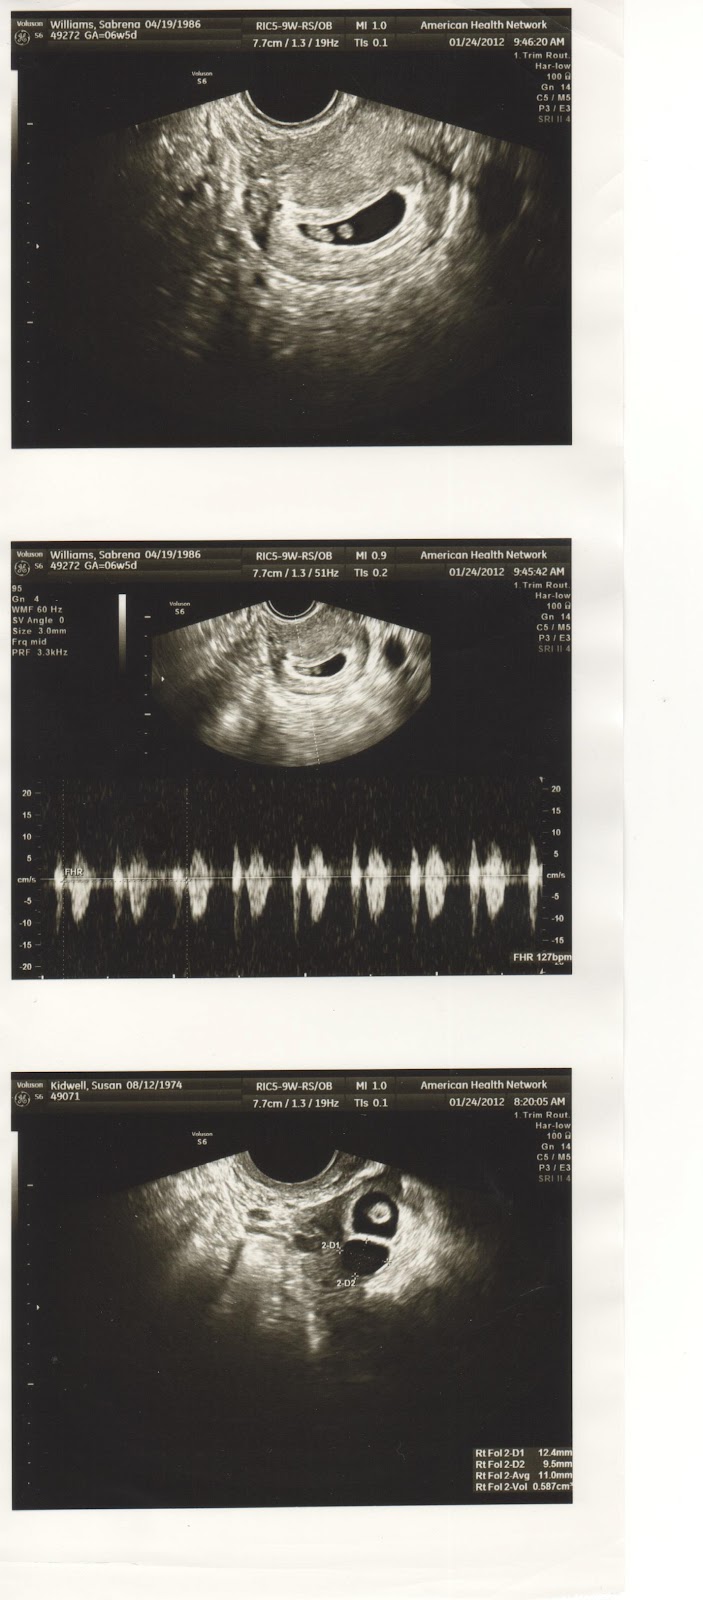

2nd Ultrasound. January 24th, 2012. 6w5d.